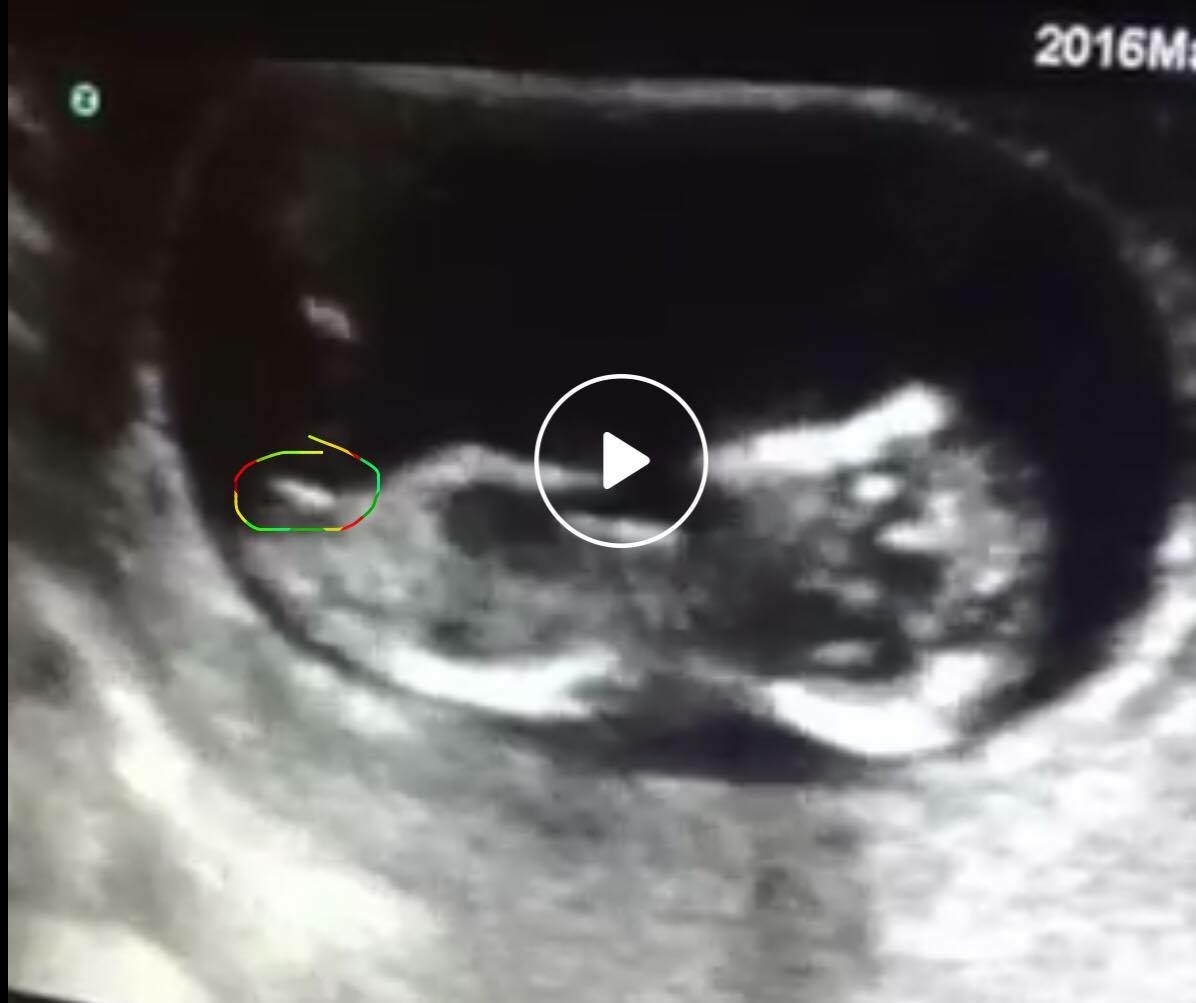

Hey guys! Brand new and wondering if anyone can guess on nub or skull. This is 12 weeks. Thanks ya'll!!! Attachment 31078Attachment 31079Attachment 31080

Could you post a link to your video here? Then I will be able to give you a better answer. I'm not sure with these screen shots.